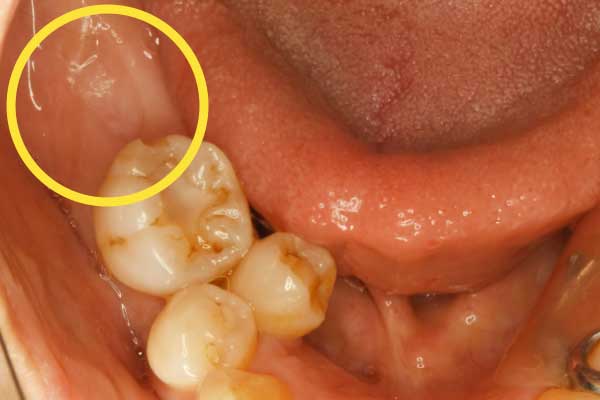

| 主訴 | 奥歯をどうにかして残したい。 他院で抜歯と言われ、インプラントが必要と診断されたが、諦めきれない。 |

|---|---|

| 治療内容 | 親知らずを活用した矯正治療 |

| 治療期間 | 準備中 |

| 治療費 | 準備中 |

| 治療の リスク | 矯正で動かす場合、数ヶ月〜数年の時間がかかる。治療中の装置により汚れが溜まりやすく、虫歯や歯周病のリスクが高まる。 |

当院では、抜かずに残しておいた親知らずを「矯正」で移動させ、奥歯として蘇らせます。

他院で「抜歯してインプラント」と言われた欠損部位に対し、当院が提案するのは、親知らずを矯正装置でゆっくりと手前に引き寄せ、空いたスペースを埋める治療法です。